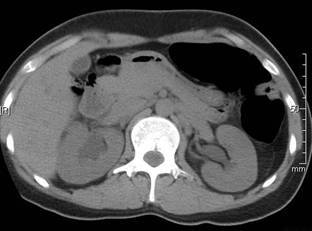

ID problem.

Hydronephrosis with overall enlargement, bilaterally.